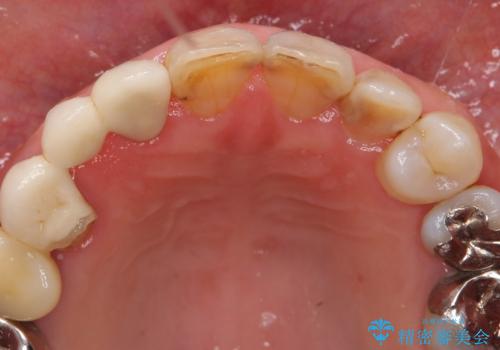

口腔内を精査したところ、右上のブリッジの内側(口蓋側)がかけており、下の前歯(右下1)には唇舌側に瘻孔を伴う大きな根尖病変ができていました。

右上のブリッジ(右上④3②)のやりかえと、下の前歯(右下1)の根管治療を行った後セラミッククラウンによる補綴治療を行いました。

右上④3②ブリッジ:オールセラミッククラウン スタンダード